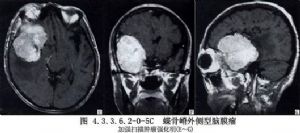

内侧型:起源于前床突与小翼内侧,肿瘤多为球形,毗邻为视神经、嗅神经、视交叉、眶上裂、颈内动脉的床突上段、分叉部、大脑中动脉和大脑前动脉的水平段、后交通动脉与海绵窦。有时肿瘤破坏眶上裂,向眼眶内生长,引起眼球突出和视力障碍。肿瘤向鞍上区及后上发展时,尚可引起垂体-下丘脑功能障碍。(图4.3.3.6.2-0-5A~C,4.3.3.6.2-0-6A~C)